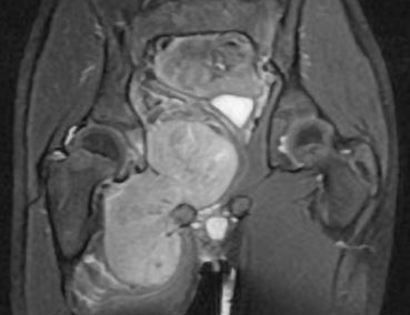

This is an MRI of the thigh region. The tumor is located in the inner right thigh (left-hand side) which is brighter than the surrounding tissues.